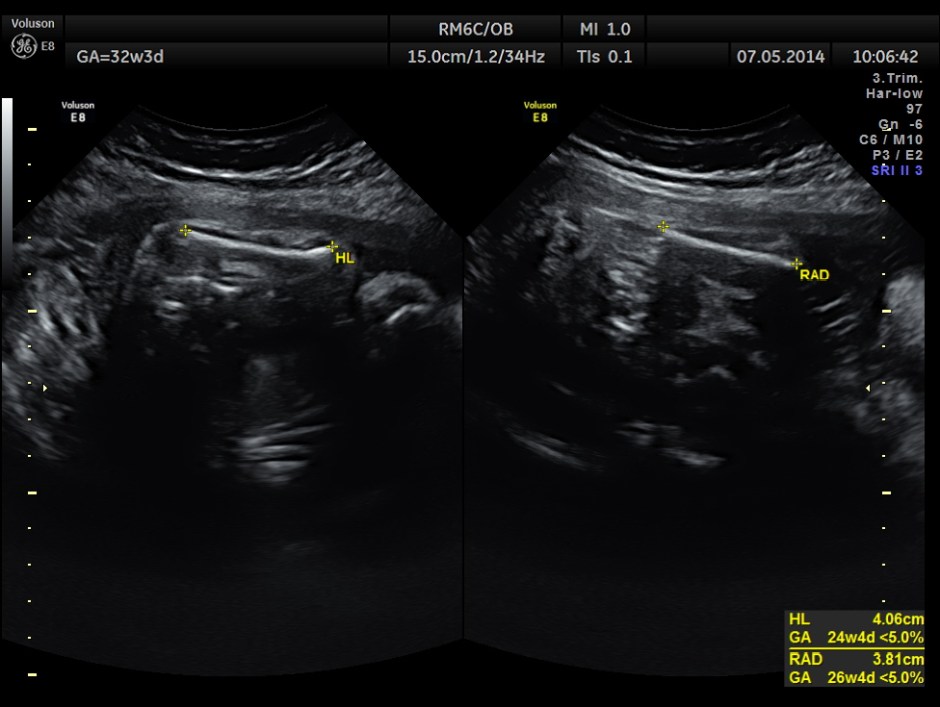

This was a 37 year old lady , a primi gravida referred for evaluation of intra uterine growth restriction. As per LMP the GA was 32 w 3 Days, but as per AUA the GA was 26 weeks . All the long bones were < 5.0 % tile. But cerebellum was 42.7 % tile. There was severe symmetrical growth restriction .

The echo pictures are given below.